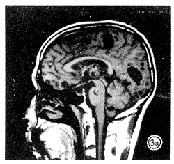

本组病例在T1WI上显示29例为圆形、类圆形囊性病变,大小多为2~8mm,最大直径达25mm,呈低信号,部分病例可见囊壁及头节,另见5例为片状稍低信号,其余10例为等信号,不能从信号强度上与正常脑实质区别。T2WI上有32例可见结节样长T2信号,8例表现为大片状高信号,未见明显囊性病灶显示,其余4例表现为阴性。T1WI+C上44例病变均见显示,其表现则多种多样:单发少见,本组病例仅见4例单发,占9%;其中3例病灶位于大脑皮层(见图1),1例位于四脑室,其余为多发,其中30例可见环形囊壁强化;3例于多发病灶中可见囊壁强化与不强化并存;8例可见囊壁及头节均强化。部分病灶的强化环可见壁皱折,囊壁厚薄不均,有的呈薄环状,有的呈中厚壁环,显示头节的病例多为薄壁,少见有水肿。

图1 (a)T2WI上示脑实质内未见明显异常高、低信号;(b) T1WI+C上示左顶叶内见环形强化影。